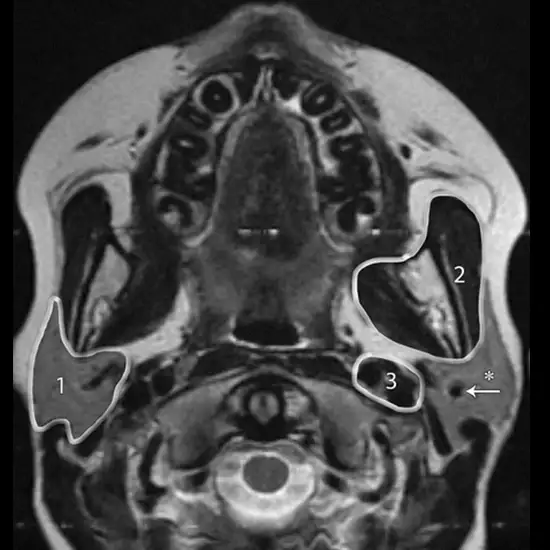

Parotid tumours are abnormal cell growths (tumours) that develop in the parotid glands. The parotid glands are two salivary glands located on each side of the face just in front of the ears. Salivary glands make saliva to help with chewing and digestion.

The deep or superficial location of the left parotid gland mass, as well as any additional mass that cannot be determined by physical examination, tumour extension, tumour contour, signal features, and the relationship between the tumour and the facial nerve, are all indicated by MRI.